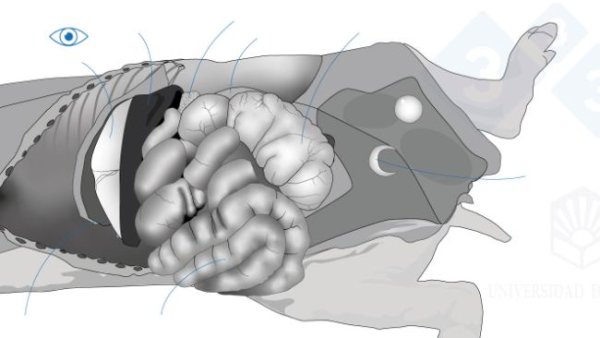

In this second installment, we cover extracting the tongue, trachea, lungs, and heart in one piece. We will extract the organs of the abdominal cavity, both the digestive system and the urinary and genital tracts. In the head, we will access the nasal turbinates, brain, and cerebellum.

In the fifth installment of the manual we address the examination of the organs of the abdominal cavity.

In the fourth installment of the manual, we address examining the thoracic cavity organs.